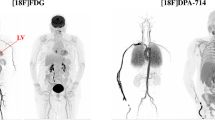

We have recently developed the TSPO PET radiotracer [18F]LW223, which has binding not susceptible to the human rs6971 genetic polymorphism and is able to detect and quantify macrophage-driven inflammation in a rat myocardial infarction (MI) model and explore the heart-brain axis that exists in this pathology [10]. This radiotracer has a distinct kinetic profile in brain versus heart, and therefore lends itself as an optimal compound for understanding the impact of different binding kinetics on outcome measures.

We and other colleagues have reported that increased TSPO in the heart due to myocardial infarction begets increased neuronal TSPO expression [5, 13]. The pathological impact of this heart-brain inflammatory axis is yet to be determined but its existence highlights the importance of seeing beyond single-organ centric analysis while pinpointing the need to characterise performance and stability of traditional kinetic models and kinetic constants. Thus far, use of these models and constants is more common in brain PET research, and their application to multiple organs with varying degrees of target expression and radiotracer kinetics has not been as widely explored compared with the use of simplified outcome measures such as SUV.

This paper aims to provide a comprehensive statistical assessment of 18F-LW223 heart and brain kinetic measures when using “gold-standard” AIF versus simplified IDIF analysis protocols of dynamic PET datasets. This is an important component of radiotracer validation, and will also provide a better understanding of some of the complexities associated with analysing the emerging heart-brain axis in the field of TSPO PET imaging.